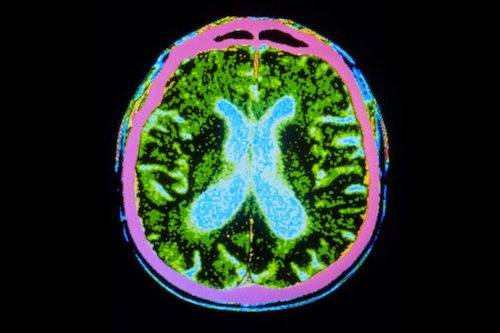

这种内部“卫星导航”系统的关键组成部分是大脑中被称为内嗅皮层的区域。这是发生阿尔茨海默症时最早被破坏的区域,这可能解释了为什么“迷路”是阿尔茨海默症的最初症状之一。然而,临床上使用的通过纸笔认知测试诊断阿尔茨海默症的方法无法检测出导航障碍。